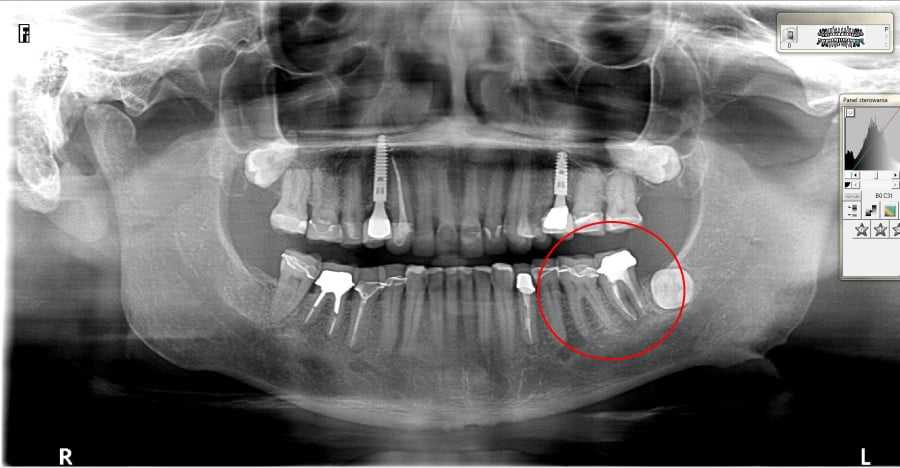

Ten problem najczęściej dotyczy zębów trzonowych żuchwy oraz górnych przedtrzonowców. Może również towarzyszyć wadom zgryzu, w zębach zniszczonych przez erozję, abrazję lub atrycję. Pionowe złamanie korzenia jest trudne do zdiagnozowania. Zdjęcia RTG nie zawsze bowiem ukaże „całą prawdę”. Coraz powszechniej używane obrazowanie CBCT (3D) pomaga w postawieniu diagnozy pionowego złamania zęba lub korzenia.

Do pionowego złamania korzenia zęba może dojść podczas zabiegu leczenia kanałowego poprzez używanie zbyt dużej siły w czasie wypełniania lub oczyszczania kanału. Może być również spowodowane zaklinowaniem się narzędzia w kanale. Pionowe korzenia zęba zawsze prowadzi do usunięcia całego zęba. Dbałość o profilaktykę i terminowe zgłaszania się do gabinetu stomatologicznego z towarzyszącą diagnostyką rentgenowską znaczącą redukuje te ryzyka.